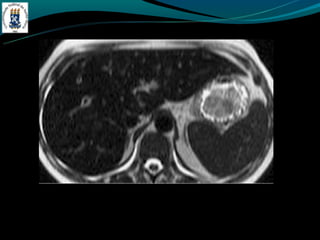

Aula figado